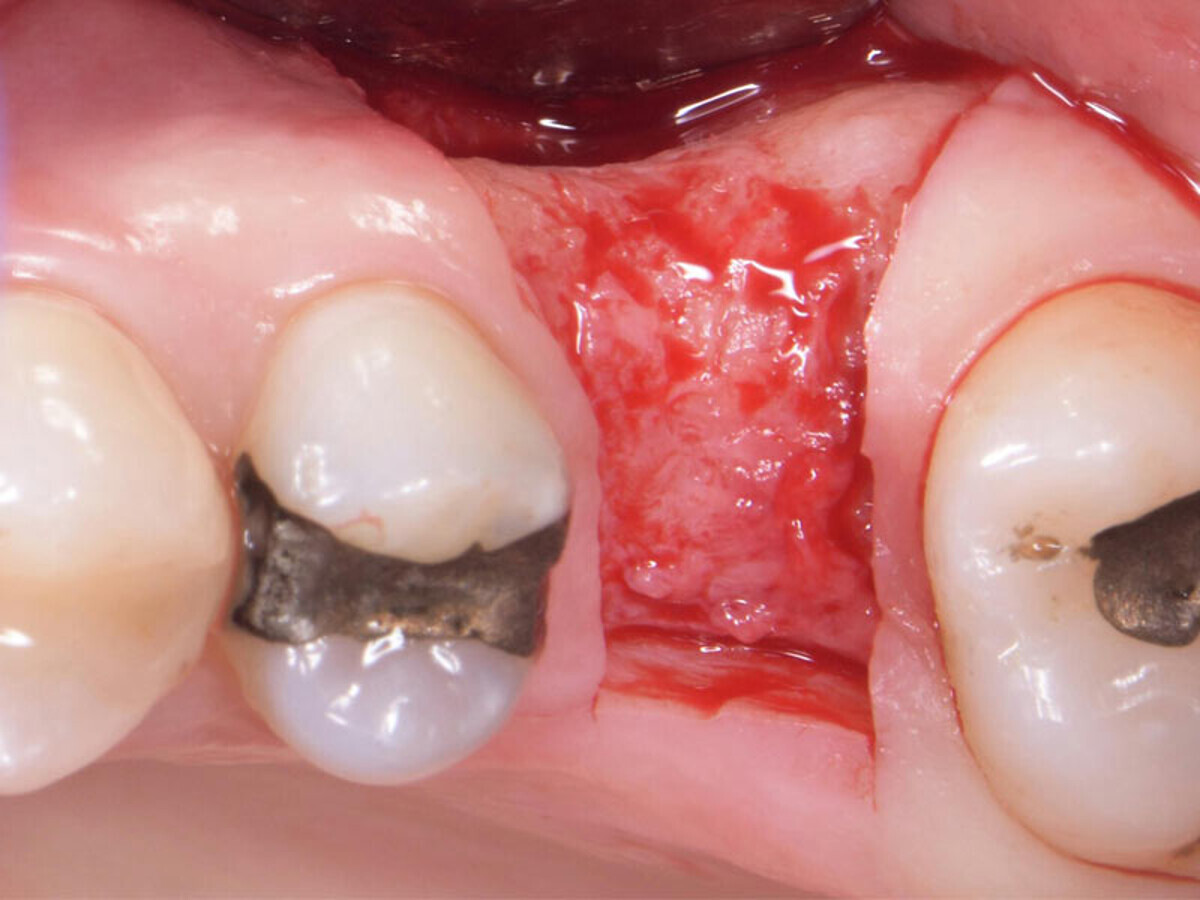

Buccal concavity.

No implant threads exposed.

Grafted with EthOss. No membranes used.